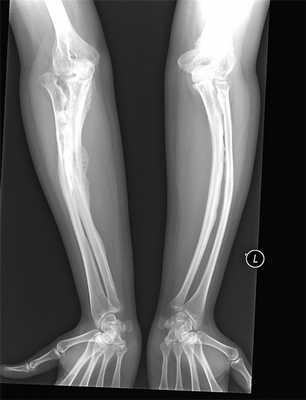

При обследовании в лабораторных данных выраженных изменений не выявлено. На рентгенограммах поперечные размеры грудной клетки уменьшены. Ребра остеопорозные, ширина их неравномерная, грудинные концы ребер, а также головки и их шейки утолщены и деформированы. Отмечалось небольшое вдавление и снижение высоты тел позвонков Th5-Th8 в центральных частях. Левая ключица деформирована в средней трети за счет костной мозоли. Кости верхних конечностей остеопорозные, отмечалась их варусная деформация. Правая плечевая кость утолщена в средней трети диафиза за счет сросшегося перелома; структура кости изменена, корковый слой истончен в области проксимального метафиза. В средней трети левой плечевой кости — линейное просветление (линия перелома). Левая лучевая кость дугообразно искривлена. Правая бедренная кость дугообразно искривлена вверх и наружу, в средней трети патологический перелом. Метафизарная часть утолщенная. Левая бедренная кость имеет саблевидную деформацию, проксимальная ее часть смещена вверх (врожденный вывих бедра). Кости голеней тоже имеют саблевидную деформацию. Череп увеличен в размерах, асимметричен, слева в теменно-затылочной области определяется дополнительная неширокая, мягко-тканная тень, прилегающая к костям свода — тень кефалгематомы. Кости свода черепа истончены, на боковой рентгенограмме прослеживаются отдельными фрагментами в виде островков обызвествления. Левая теменная кость выбухает (состоит из отдельных фрагментов). Швы черепа почти не прослеживаются (рис. 2-3).

Рисунок 2. Рентгенограмма костей черепа

Fig. 2. Radiograph of the cranial bones

Рисунок 3. Обзорная рентгенограмма костей скелета

Fig. 3. Survey film of skeletal bones